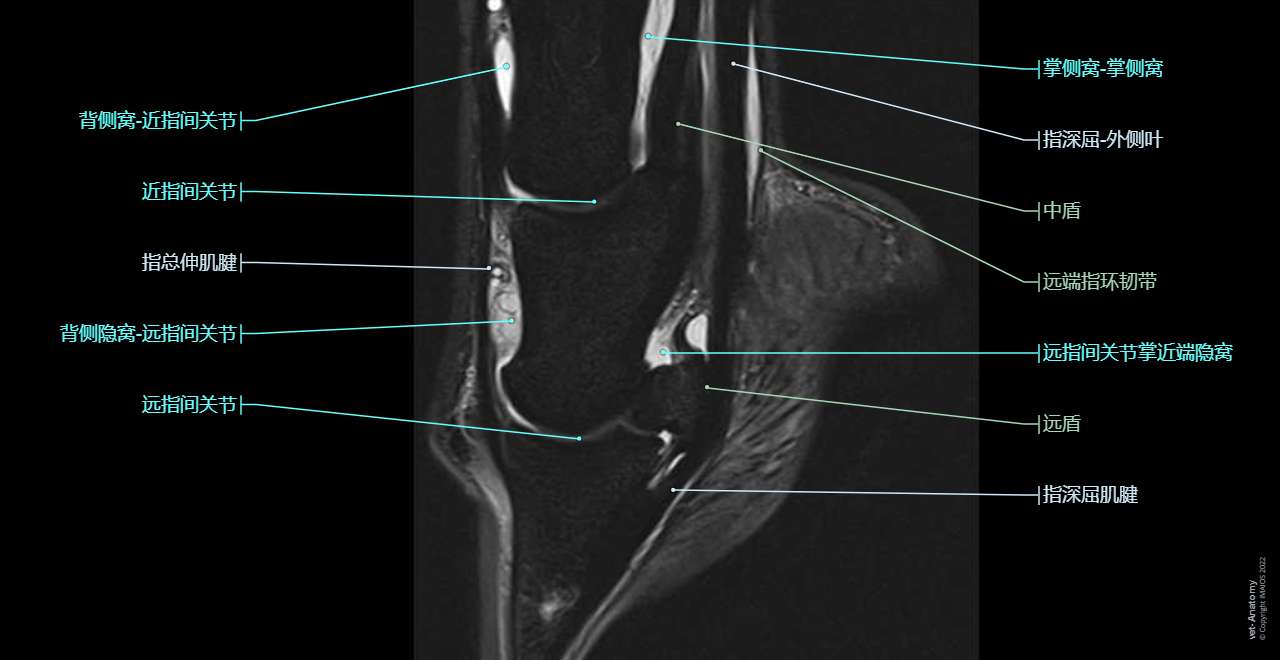

Anatomy of the equine digit on Magnetic Resonance Imaging (MRI): Superficial digital flexor tendon [SDFT], Common digital extensor tendon, Deep digital flexor tendon [DDFT], Proximal interphalangeal joint [Pastern joint; PIP joint], Distal interphalangeal joint [Coffin joint; DIP joint]

这单元展示马足趾(马蹄、足和骹)核磁共振MRI解剖图。

这单元的马足趾核磁共振解剖图是由Gwendolyn J. Levine(DVM, DACVP)提供。德克萨斯A&M大学的兽医与生物医学学院使用Siemens Verio 3T核磁共振机器扫描美洲奎特马正常左前腿。